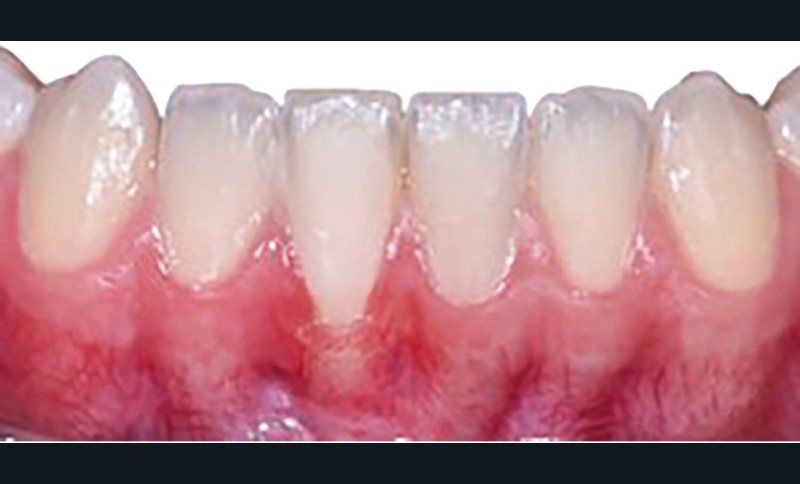

La greffe épithélio-conjonctive (GEC) [7, 8] consiste au remplacement du tissu parodontal existant par un greffon épithélio-conjonctif dont l’indication principale est l’augmentation en hauteur et en épaisseur du tissu kératinisé (fig. 2). Elle peut aussi être utilisée dans le recouvrement radiculaire (avec des résultats en termes de recouvrement inférieurs à ceux des techniques de greffe de conjonctif enfouie), l’aménagement des crêtes édentées, l’aménagement péri-implantaires [9, 10] (fig. 3), ou en association avec un traitement ortho-parodontal [11]. Le principal défaut de cette technique est son aspect inesthétique ; elle sera donc réservée à des zones non visibles comme les incisives mandibulaires ou les zones postérieures.